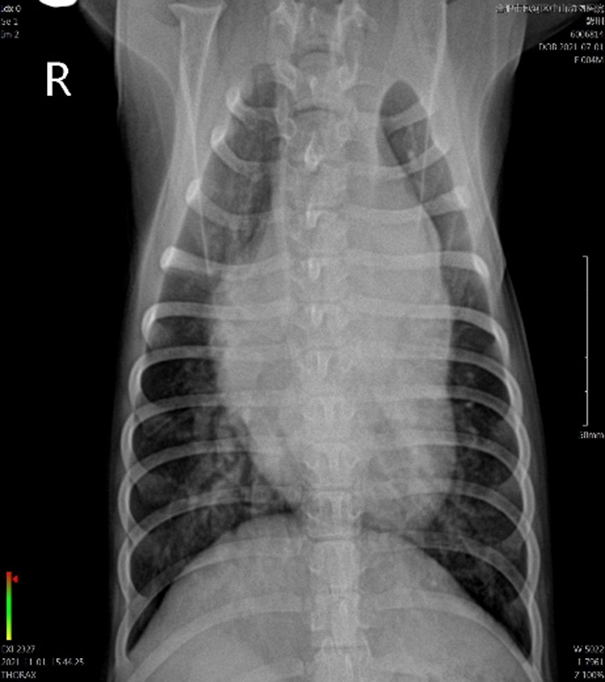

1.2.3影像检查

DR胸部正侧位片可见气管上抬,左心房增大,正位片可见肺动脉膨出,VHS=11.9v,心脏彩超右侧长轴可见左心室增大,左心房增大,二尖瓣返流,LA/AO=1.64,PA:AO=1.24,LVIDD=44.23cm,左心容量过载,肺动脉扩张,右侧头侧短轴切面,可见持续性湍流从动脉导管流入肺动脉,血流速度过快。

综合听诊,胸片及心超可确诊为先天性心脏病动脉导管未闭,从左到右分流,伴有左心容量过载,左心舒张功能亢奋,收缩功能下降。

该犬术后当天24小时看护,监测血压心率,给与对症消炎预防感染,术后持续给与镇痛泵和皮下镇痛导管推注布比卡因,每天给与匹莫苯丹。术后三小时,该犬可以主动吃东西,术后第二天,开始下地小跑,术后第三天,拔除皮下镇痛导管,术后第五天,由于胸腔积液小于每天每公斤体重2.2ml,拔除胸导管。术后第七天复查心超+胸片,VHS=9.8v,左心房减小,LA/AO=1.24,PA/AO=0.96,LVIDD=3.05cm,肺动脉湍流消失,术后该犬明显变的活跃,同时该犬E波明显下降,肺动脉瓣口出现轻度返流,肺动脉湍流的血流也消失了。